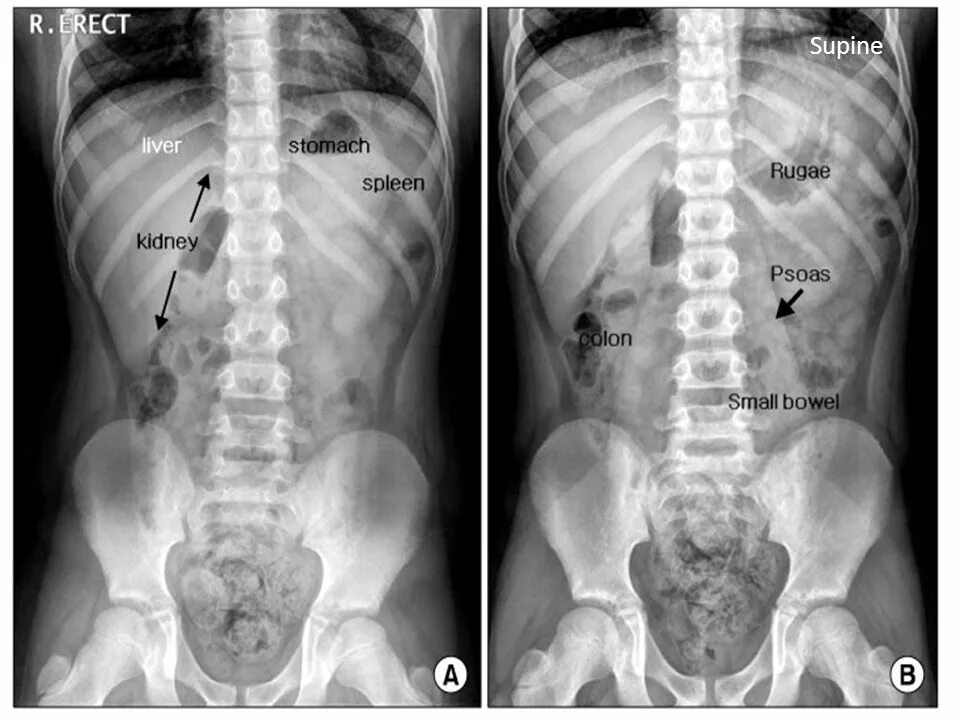

Псоас симптом